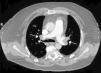

Ante los datos gasométricos (hipoxemia con hipocapnia) y la disnea de rápida instauración, se realizó una TAC de arterias pulmonares, por sospecha de tromboembolismo pulmonar (TEP) (fig. 1).

Se confirmó el diagnóstico de TEP con afectación de la práctica totalidad del árbol pulmonar, desde ramas segmentarias a principales, así como imágenes en relación con trombosis venosa profunda (TVP) en vena poplítea derecha.